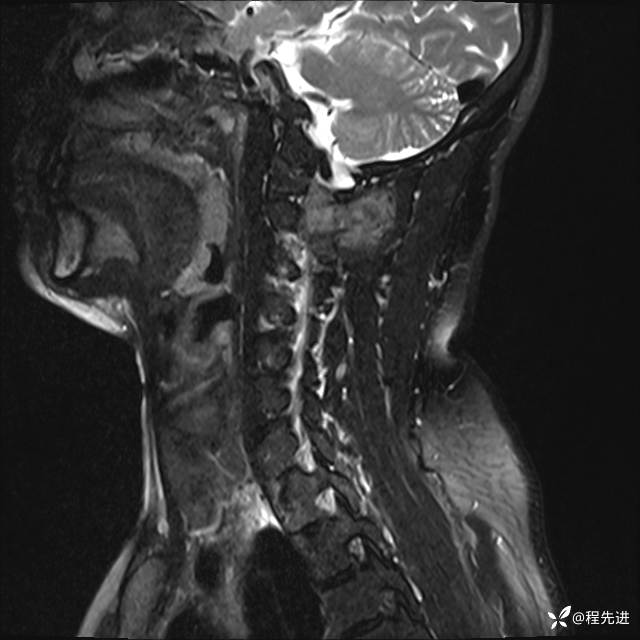

MRI平扫+增强:

T2: